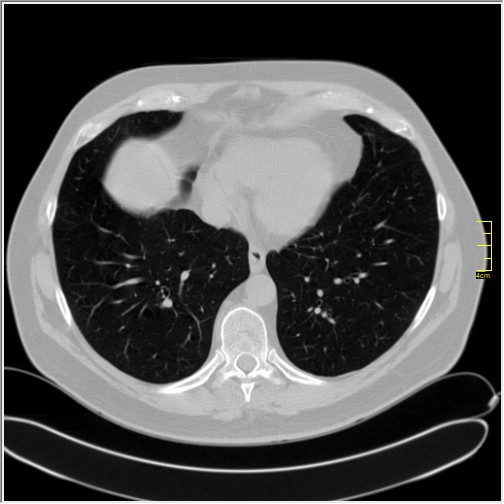

Pacijent prvi put dolazi 3 dana nakon pojave simptoma a dva dana nakon pozitivnog testa. Ima temperaturu koja tek prelazi 37. Ne kašlje, testirao se kao kontakt. Oseća mirise i ukuse. Po laboratoriji pulmolog koji ga je pregledao misli da je moguće da se radi o nekom novom soju. Nije vakcinisan. Nije ni antivakcinaš. Jednostavno je mislio da sačeka.

Severity score 0/25. Najdraže mi je kada vidim to.